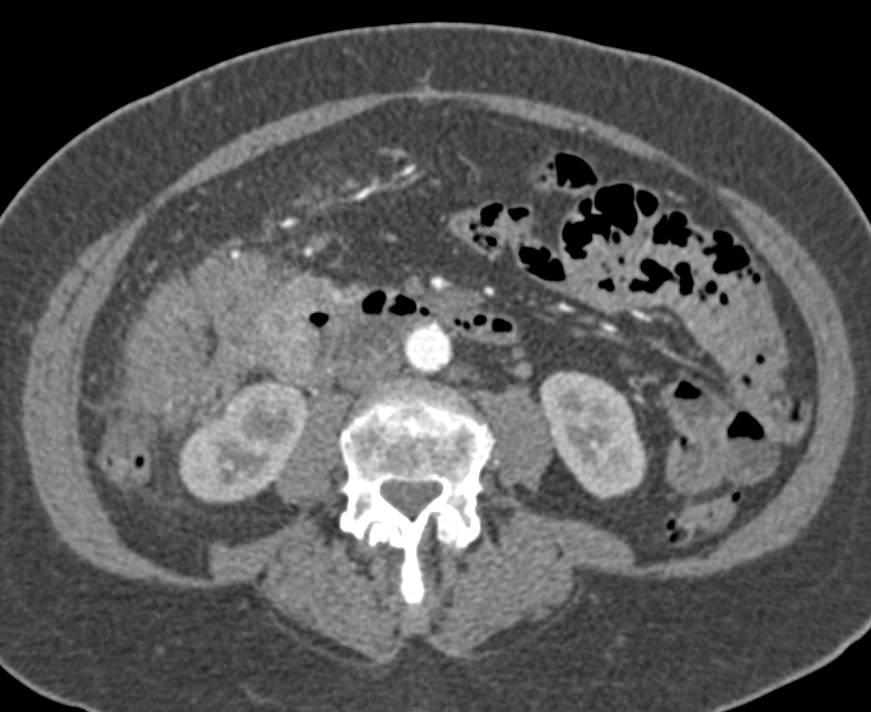

Appendiceal Abscess Involves the Abdominal Wall